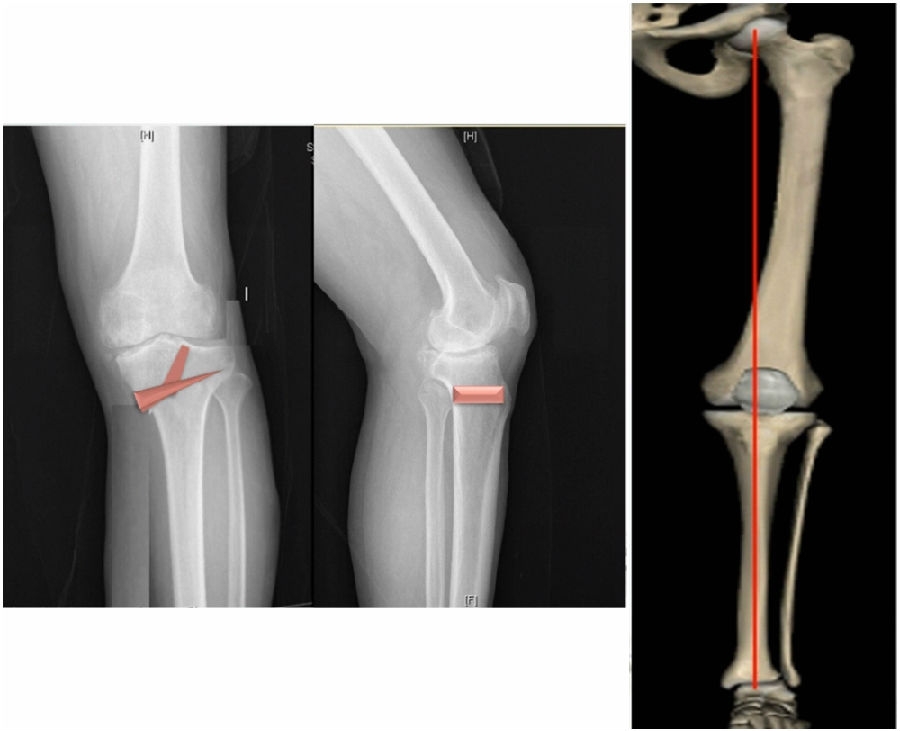

典型病例,女性,56岁,农民右膝内翻18度。

术前影像

结合影像学来看,该患者单纯用闭合截骨或开放截骨,对肢体均有影响,所以决定采用混合型截骨。术中混合截骨旋转中心选在内外1/3处,先做闭合楔,然后顺势将开放楔敲开,达到术前设计的目标力线。术后随访力线达到要求。

术后X线